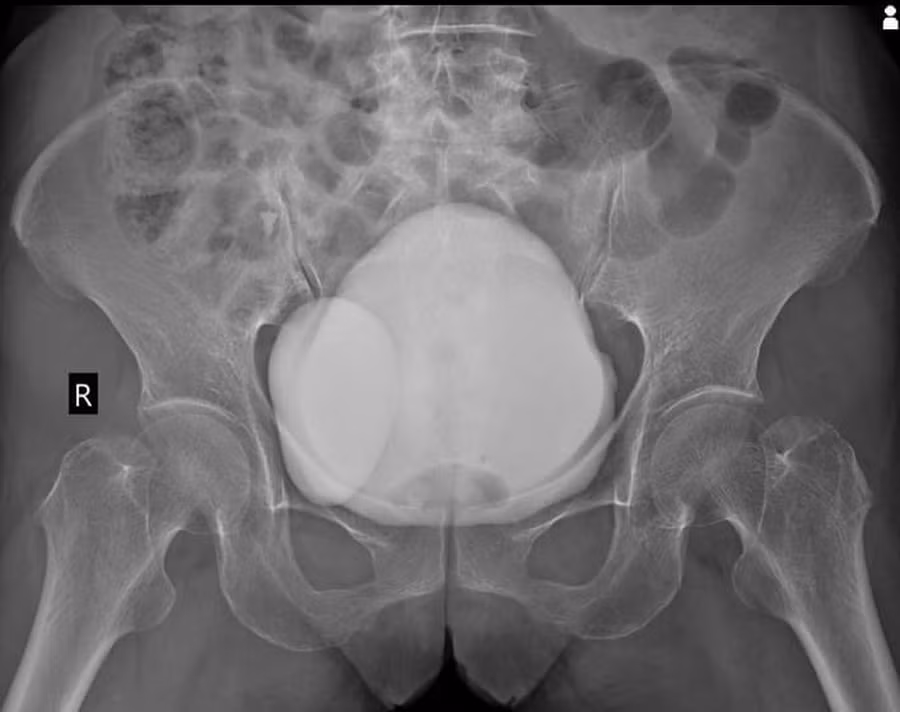

| Hình ảnh chụp CT cho thấy bệnh nhân có túi thừa bàng quang. |

Theo ThS.BS Nguyễn Thế Thịnh – Khoa Phẫu thuật tiết niệu và Nam học (Bệnh viện E), túi thừa bàng quang là tình trạng xuất hiện túi phồng bất thường hình thành trên thành bàng quang.

Túi được hình thành do sự thoát vị của lớp niêm mạc bàng quang qua lớp cơ bàng quang. Túi thừa bàng quang có thể nằm ở bất kỳ vị trí nào trên bàng quang, nhưng phổ biến nhất là ở mặt sau.